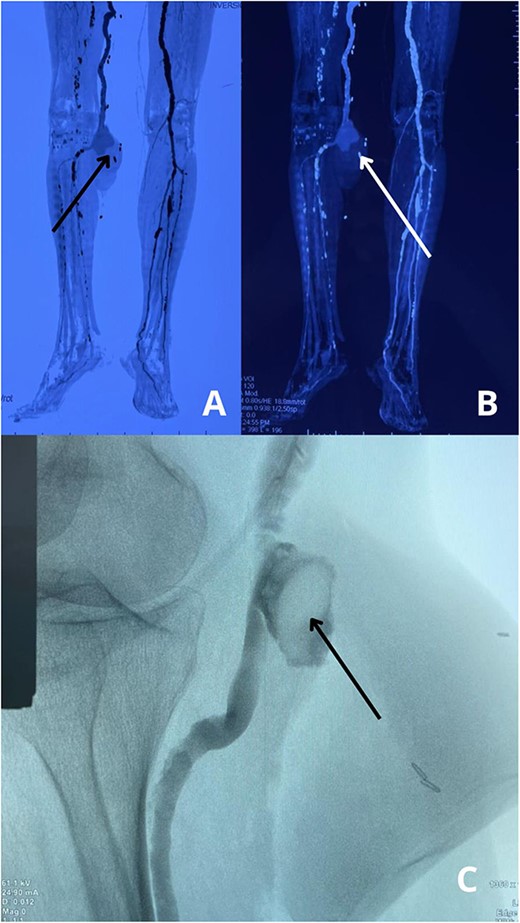

An ultrasound Doppler revealed turbulent blood flow within a pseudoaneurysm from the popliteal artery. A computed tomography angiogram (CTA) confirmed a 45 × 40 mm pseudoaneurysm with a small arterial tear and a surrounding hematoma compressing adjacent structures (Fig. 2A–C). The CTA also updated the size of the AAA, now 55 mm, requiring careful planning for surgical intervention to prevent rupture while addressing both vascular issues.

(A, B) CTA scans of the lower extremities reveal a pseudoaneurysm in the right popliteal artery, indicating vascular injury with disrupted arterial flow. (C) Angiographic study shows the pseudoaneurysm sac and confirms a tear in the popliteal artery, with no evidence of distal thrombus or embolization.